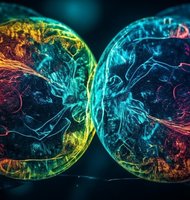

Nanomateriál zregeneroval chrupavku v kolene

Výskumníci z Connecticutskej univerzity úspešne obnovili poškodenú chrupavku v kolennom kĺbe králika pomocou biologicky odbúrateľných polymérov s piezoelektrickými vlastnosťami. Artritída je často diagnostikované ochorenie, ktoré spôsobuje poškodenie chrupaviek chrániacich naše kĺby. Môže to viesť k takému opotrebovaniu chrupavky, že sa kosť začne trieť o kosť, čo spôsobuje, že každodenné činnosti, ako je napríklad chôdza, sú veľmi bolestivé.

Súčasná liečba zahŕňa fyzioterapiu a lieky proti bolesti, ale ťažké prípady si často vyžadujú chirurgický zákrok, pri ktorom sa poškodená chrupavka nahradí zdravou chrupavkou odobratou z inej časti tela alebo od darcu. Tím pod vedením bioinžiniera Thanha Nguyena teraz navrhol liečbu, ktorá využíva elektrické signály na stimuláciu regenerácie chrupavky.

Do kolena králika s poškodenou chrupavkou výskumníci implantovali tkanivové lešenie vyrobené z nanovlákien kyseliny polymliečnej (PLLA), biologicky odbúrateľ ...